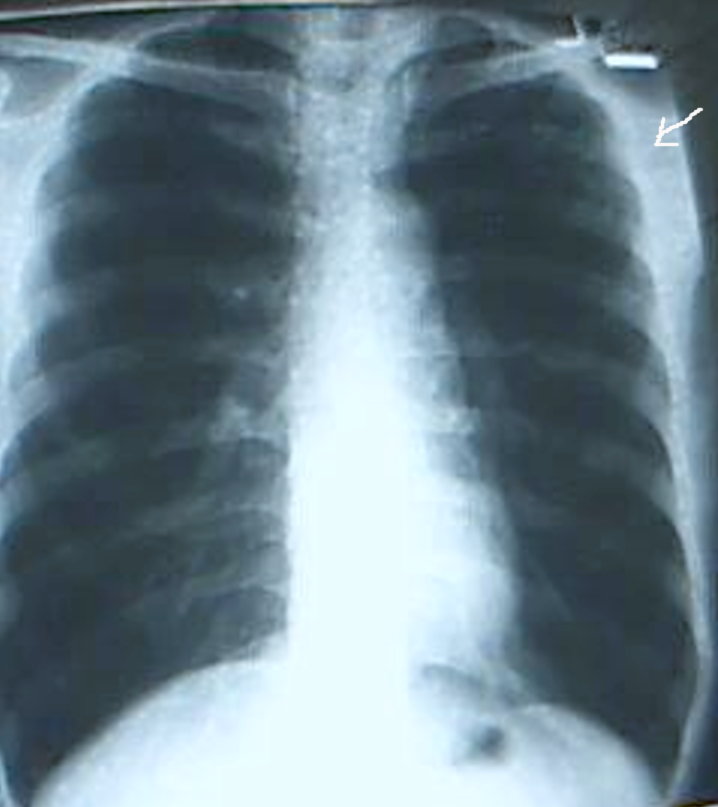

标题: 补一个

补一个

图像质量不好,就现有后前位胸片看,可疑左上肺胸膜下结节,左三四后肋溶骨性破坏。肺癌肋骨转移?

图像质量不好,就现有后前位胸片看,左三、四、五后肋溶骨性破坏。考虑转移。原发灶待查。[emb7][emb14][emb28][em14]

左三、四、五后肋溶骨性破坏。考虑转移。原发灶待查。